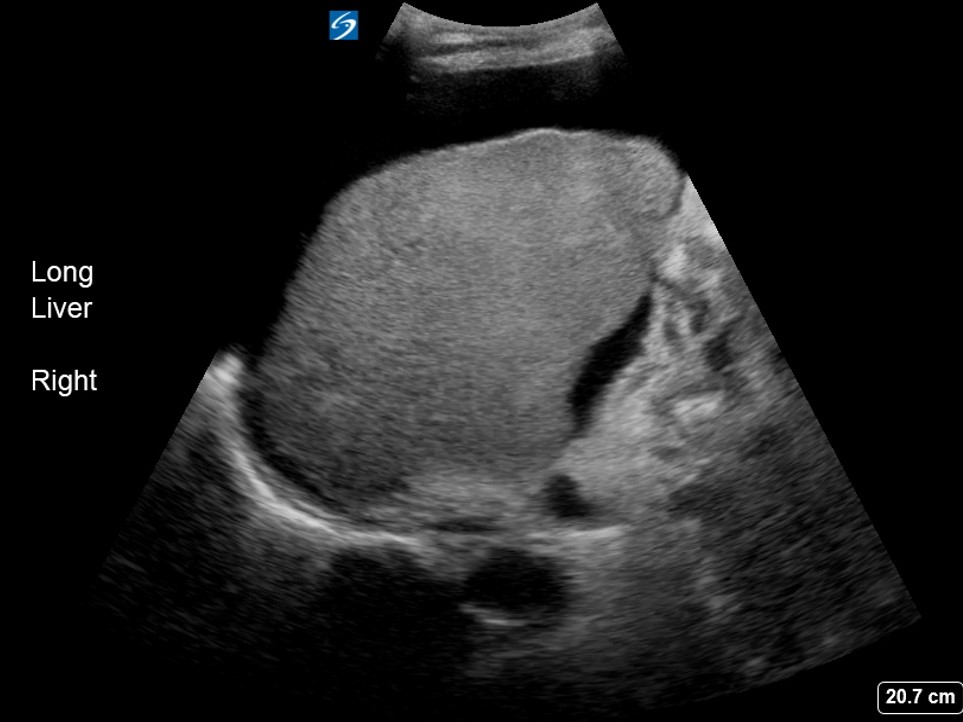

Preoperative liver ultrasound showing cirrhotic liver. Download